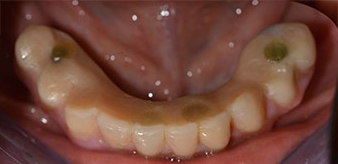

La paciente de 64 años se presentó con una dentición residual compuesta por las piezas dentales 38, 33 y 43 en el maxilar inferior y con una prótesis temporal fijada con ganchos en el maxilar inferior (figs. 1 y 2).

Tras explicarle las distintas opciones de tratamiento, la paciente se decidió por la extracción de la dentición residual en el maxilar inferior, la implantación inmediata y el tratamiento con el método Fast & Fixed (bredent medical), con el que la prótesis dental fijada provisionalmente se atornilla sobre cuatro implantes en el mismo día de la intervención. El objetivo era operar a la paciente el viernes para que el lunes pudiera tomar parte en los exámenes orales para la prueba de acceso a la universidad.

Para la planificación y la minimización del riesgo, se realizó una tomografía volumétrica tridimensional (TVD, Planmeca) que mostró que la calidad y la cantidad del tejido óseo era suficiente para la intervención quirúrgica y el tratamiento inmediato con el método Fast & Fixed. Siguiendo el protocolo de este método, se insertaron los implantes en la región de las piezas 35, 32, 42 y 45. Debido a la inclinación de hasta 45 grados de los implantes distales, el perfil de emergencia se desplazó hacia posterior y se generó un mayor polígono de soporte (fig. 3).